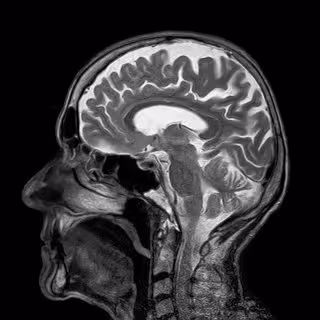

Cerebro

PIXABAY - Archivo